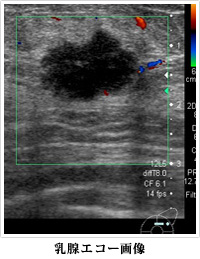

4. 乳腺エコー(超音波検査)

皮膚にゼリーを塗って超音波を当てることで画像を得ることができる検査です。

被爆の心配は全くありません。

身体の中の腫瘍に対して、実際のエコー画像を観察しながら針で組織や細胞を採取することができます。

マンモグラフィーに加えて乳腺エコーを追加することによって、総合的に乳がんの診断をおこなうことができます。